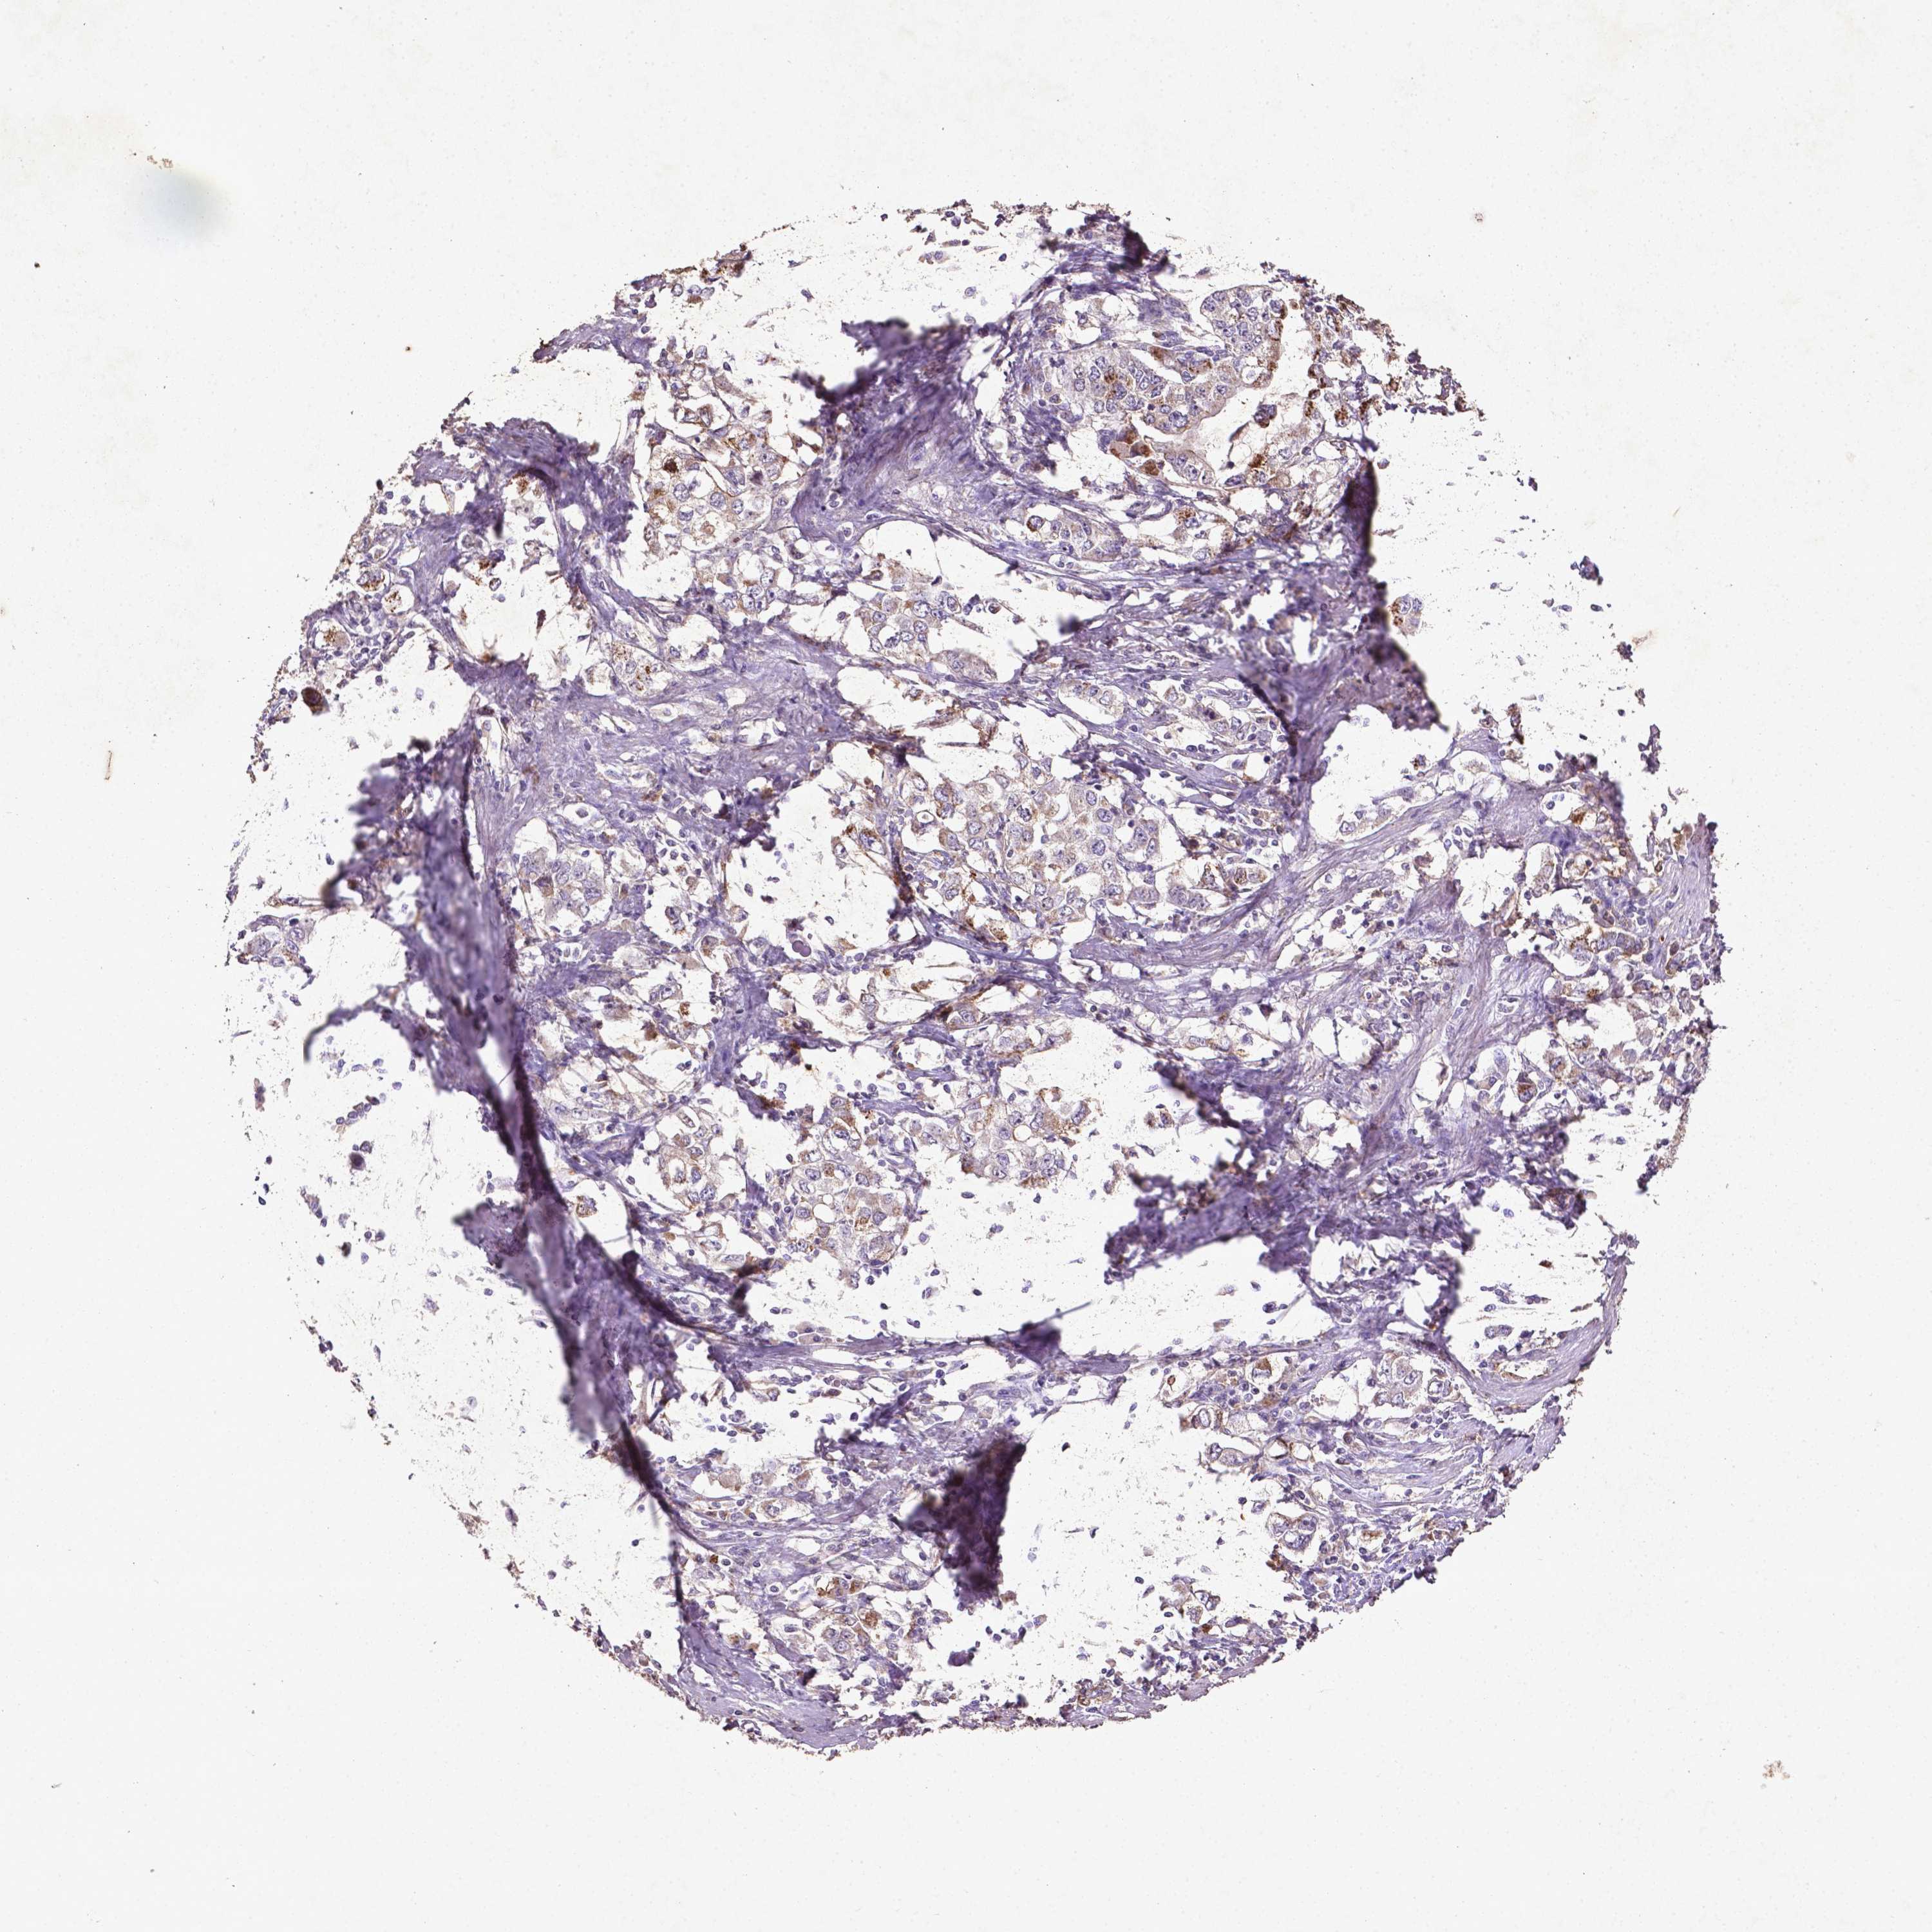

STOMACH CANCER - Protein expressioni

A mouse-over function shows sample information and annotation data. Click on an image to view it in a full screen mode. Samples can be filtered based on level of antibody staining by selecting one or several of the following categories: high, medium, low and not detected. The assay and annotation is described here.

Note that samples used for immunohistochemistry by the Human Protein Atlas do not correspond to samples in the TCGA dataset.

Antibody stainingi

Antibody staining in the annotated cell types in the current human tissue is reported as not detected, low, medium, or high, based on conventional immunohistochemistry profiling in selected tissues. This score is based on the combination of the staining intensity and fraction of stained cells.

Each image is clickable and will lead to virtual microscopy that enables deeper exploration of all samples and also displays staining intensity scores, fraction scores and subcellular localization as well as patient and tissue information for each sample.

CAB069425

CAB080053

CAB080065

CAB080070

CAB080081

CAB080095

CAB080097

Staining

High

Medium

Low

Not detected

Intensity

Strong

Moderate

Weak

Negative

Quantity

>75%

75%-25%

<25%

None

Location

Nuclear

Cytoplasmic/membranous

Cytoplasmic/membranous,nuclear

Adenocarcinoma, NOS

Adenocarcinoma, High grade